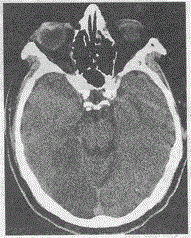

问题 男,56岁,高血压病史4年,视力模糊3天,头颅CT平扫如图,最可能的诊断是

选项 A.星形细胞瘤 B.蛛网膜囊肿 C.胆脂瘤 D.缺血性脑梗死 E.脑炎

答案 D